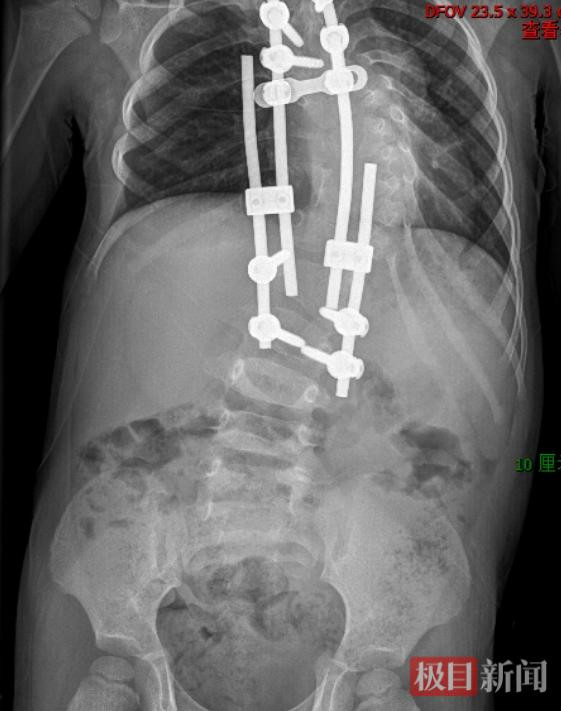

2015年,2岁半的可可在武汉儿童医院接受了一期手术,专家在她的胸椎、腰椎植入4根生长棒和8枚椎弓根钉当“支架”,尽可能给扭曲的脊柱以支撑,延缓侧弯的进展,同时为胸腔和内脏争取生长空间。

此后的9年时间,可可每年接受一次调整手术。周治国团队根据生长和矫正情况,对生长棒进行延长和调整,一点点“掰直”扭曲的脊柱。最终,可可脊柱侧弯的度数从90度降至72度,这也为后期手术争取到机会。

第一次手术后,孩子脊柱扭曲状态得到了控制